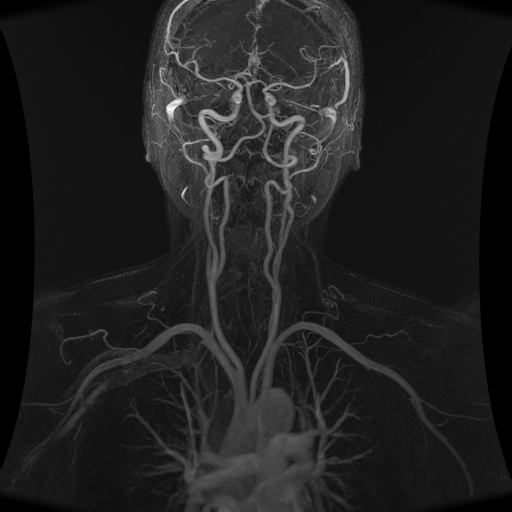

Les sténoses carotides apparaissent le plus souvent chez les patients de plus de 55 ans. Le plus souvent la sténose carotide, lorsqu’elle est peu importante, ne donne aucun symptôme : elle est dite asymptomatique. Elle est alors découverte par un examen Echo-Doppler, plus rarement par un examen angioscanner ou angio-IRM.

Si la sténose est supérieure à 60 %, un angio-scanner le plus souvent, ou une angio–IRM sera demandé pour préciser le degré de la sténose, analyser les autres artères irrigant le cerveau ainsi que le tissu cérébral afin d’évaluer les conséquences de la sténose sur la vascularisation du cerveau.